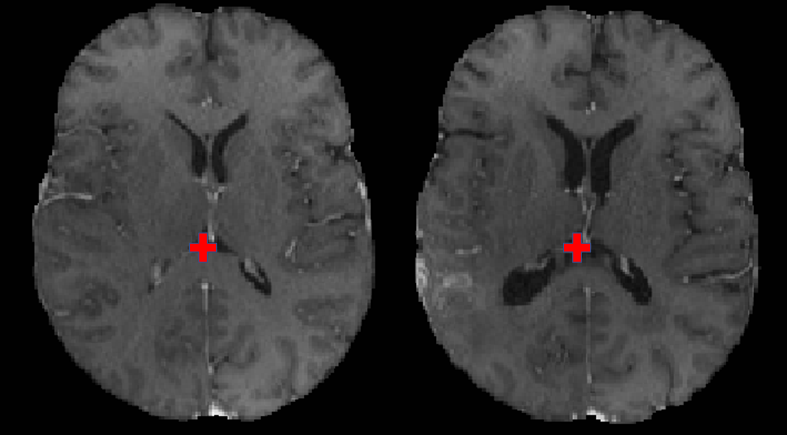

Refer to caption

Figure 2: An example of corresponding pair of landmark point in Baseline (left) and Follow-up (Right) superimposed on t1ce scan for visualization

The clinical experts of our team (H.A., M.B., B.W., J.S., E.C., J.R., S.A., M.M.) were provided with the segmentation of intra-tumor parts (i.e., the tumor core that is the potentially resectable region [35]) and specific instructions of a common annotation protocol. Specifically, for each pre-operative scan, an expert places χ𝜒\chi landmarks near the tumor (within 30mm) and ψ𝜓\psi landmarks far from the tumor (beyond 30mm). Subsequently, the expert identifies the corresponding landmarks in the post-operative scan. The landmarks are defined on anatomically distinct locations, such as blood vessel bifurcations, the anatomical shape of the cortex, and anatomical landmarks of the midline of the brain. Fig. 2 shows a sample landmark point marked in baseline scan along with the location of its corresponding landmark in the follow-up scan. The total number of landmarks (χ𝜒\chi+ψ𝜓\psi) vary for each case between 6 and 50. The annotators are given the flexibility to use their preferred tool (including MIPAV, CaPTk, and ITK-SNAP) for making the annotations and we then convert all of them into a common .csv format.